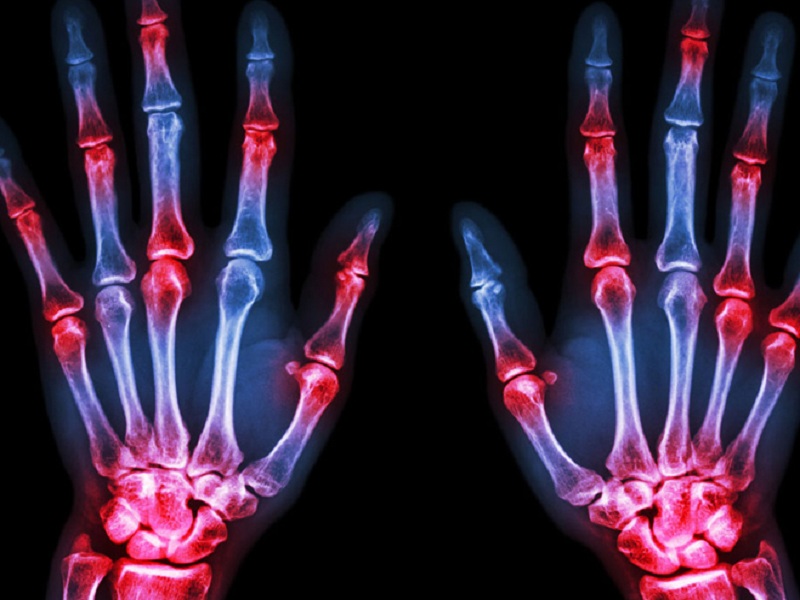

Artrite reumatoide: il trattamento con la terapia di combinazione o con i farmaci biologici abbatte anche il rischio diabetico

Stando ai risultati di uno studio pubblicato su RMD Open, i pazienti affetti da artrite reumatoide (AR) presenterebbero un rischio minore di sviluppare il diabete quando in trattamento con una terapia di combinazione (MTX + DMARDcs o non DMARD) o con farmaci biologici da soli, rispetto alla monoterapia con metotrexato (MTX).